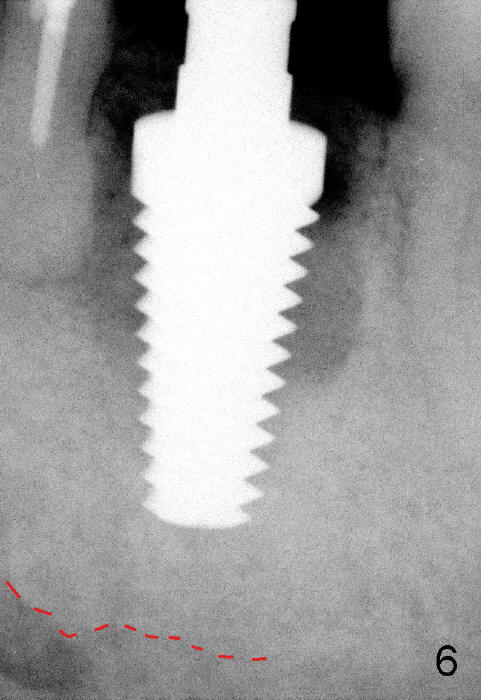

When a 7x17mm tap is inserted, it is stable. There is distance to the inferior alveolar nerve (Fig.6: dashed line).

Prior to implant placement (Fig.7,9: 7x17 mm with insertion torque 40 Ncm), a mixture of autogenous bone (Fig.8 red particles) and demineralized cortical allograft (white granules) is packed against defective socket walls, particularly apically. It leaves a space in the middle of the socket for implant insertion later on. In this case, the buccal wall around the apex, corresponding to the fistula (Fig.9 >) is severely destroyed, whereas the crestal portion is more or less intact. Three months later, the implant appears yet to osteointegrate (Fig.10), while the fistula disappears (Fig.11). The large implant does not look too overengineered over the alveolus (Fig.12 (lingual view). In fact, the implant has mild mobility. How to fix it?